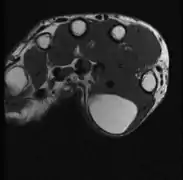

Diagnosis

A physical exam is typically the easiest way to diagnose it. Rarely, a tissue biopsy or imaging may be required. The imaging modality of choice is magnetic resonance imaging (MRI), because it has superior sensitivity of distinguishing it from liposarcoma as well as mapping the surrounding anatomy.[20]